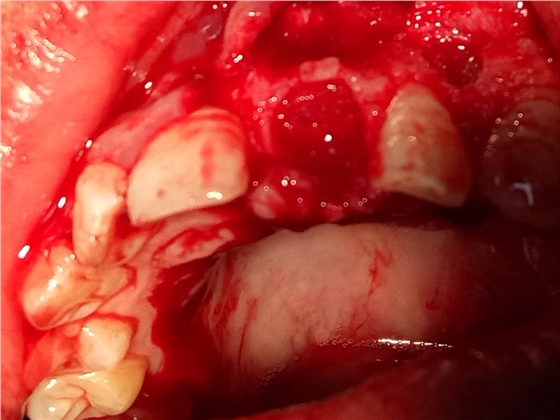

死髓牙2度,沒保留價值了,外傷造成的外吸收,即使到充也容易出問題。和患者溝通,要求做種植,用了兩個骨膠原,側切、尖牙沒事,側切做了一次根充